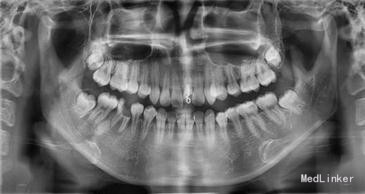

检查:21 自凝树脂桩核修复,树脂冠略有松动,叩诊无明显不适,唇侧牙龈有一陈旧性瘘管。

X-ray显示根管治疗不完善。

诊断:21不良修复体